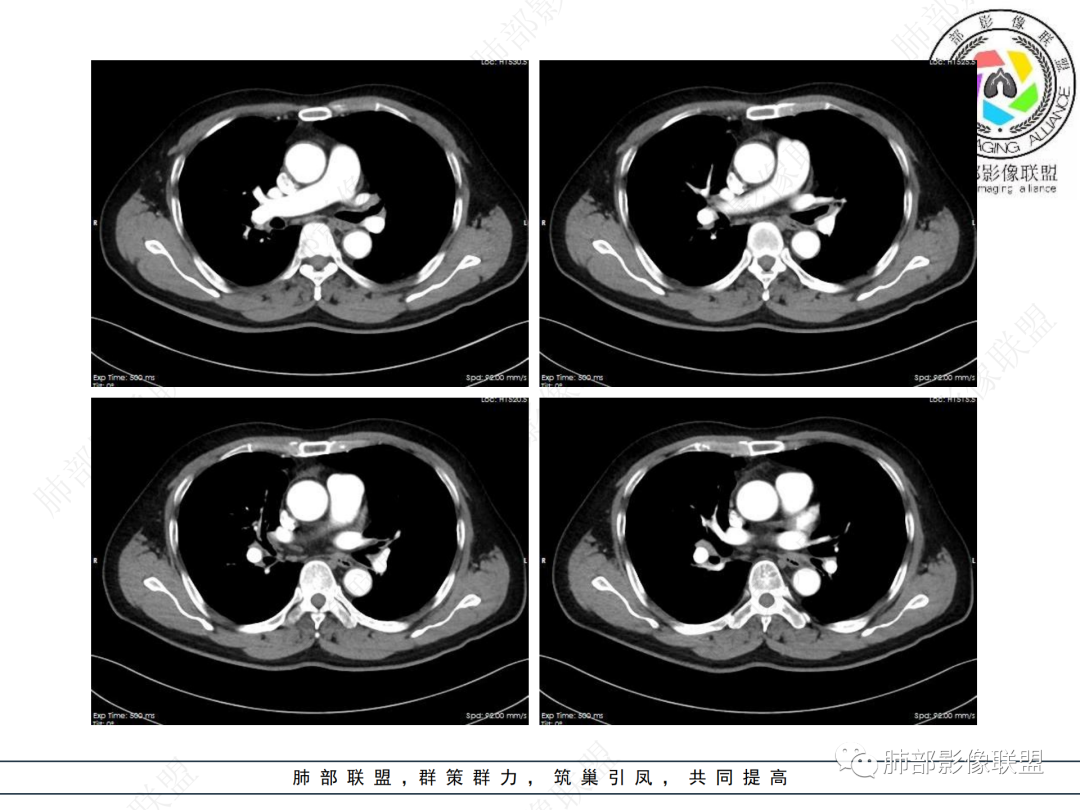

主要在慢性炎性病变与腺癌之间鉴别,病灶有膨胀性生长,支气管未见阻塞,支气管僵硬,增强病灶内可见强化,支气管内部壁增厚,偏向占位性病变,腺癌可能。

病史2年。右肺上叶团片影,边缘部分清晰,平直,相邻纵隔侧胸膜黏连较广泛,周围见斑点。增强均匀强化。首选炎性肉芽肿性病变(慢性炎症,结核)。肿瘤性病变待排。食道上段形态异常建议相关检查。

结合本病例,老年男性患者,慢性病程,急性加重,无吸烟史,影像学表现为右肺上叶尖后段斑片实变密度影,整体边界清晰,边缘平直收缩为主,周边散在纤维条索影,内部见支气管内粘液栓,血管影走形正常,没有明显破坏,增强扫描明显强化,缺乏典型分叶毛刺、胸膜改变,病灶也未显示清楚的磨玻璃勾边,病灶大而肺门纵隔未见肿大淋巴结,综合考虑慢性炎性肉芽肿可能性大。但恶性,结核能完全排除吗?我想对临床医生来说还是有很大考验的。